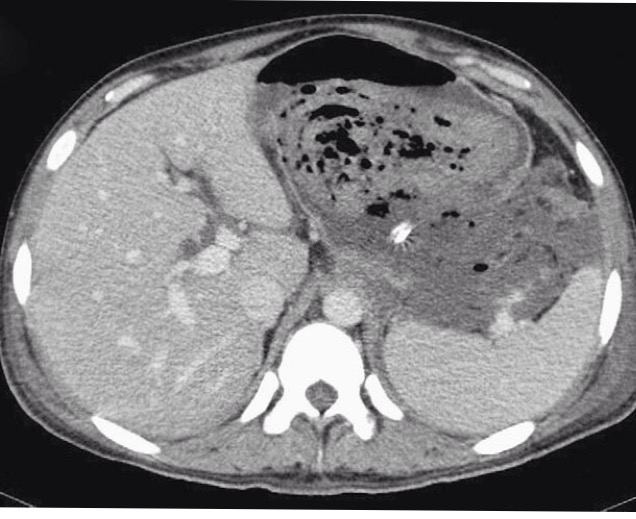

There was an eccentric thrombus in the superior mesenteric vein at its junction with the splenic vein, but the splenoportal axis was patent. The patient then underwent endoscopy, which revealed a normal esophagus, and a large clot was seen along the lesser curvature of the stomach. Multiple fistulous tracts were seen on the posterior wall of the stomach leading into the peritoneal cavity (Fig. 2).

![]() |

| Fig 2 EGD showing peritoneal cavity pancreato gastric fistula |